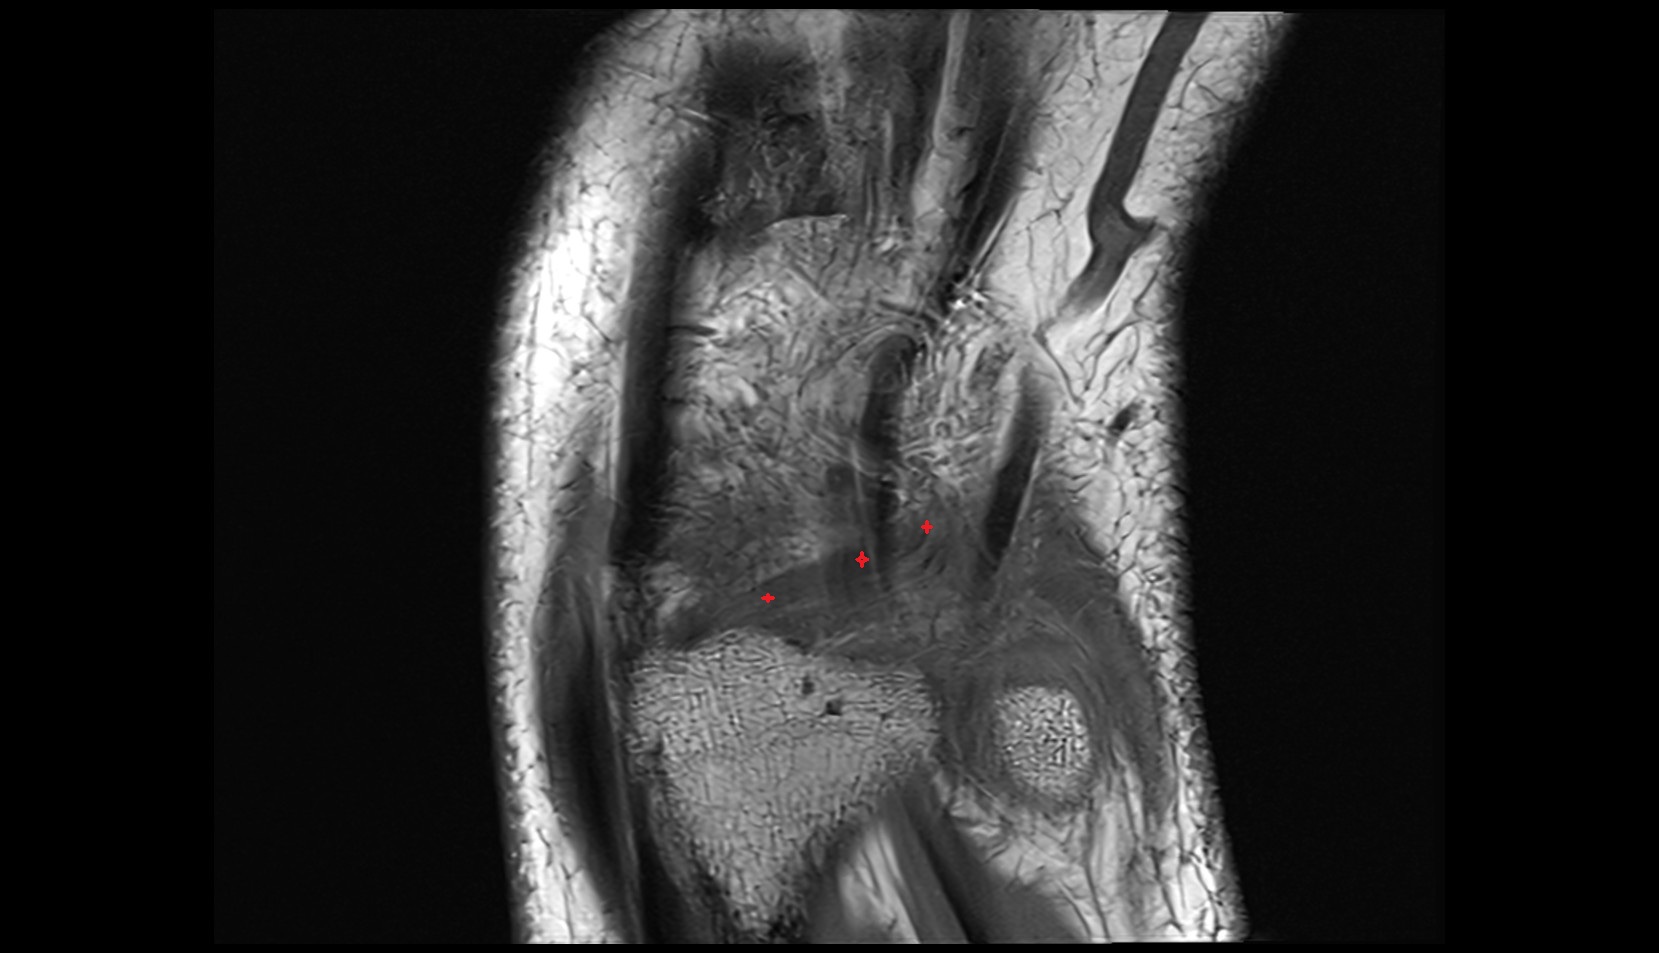

- Knee Joint